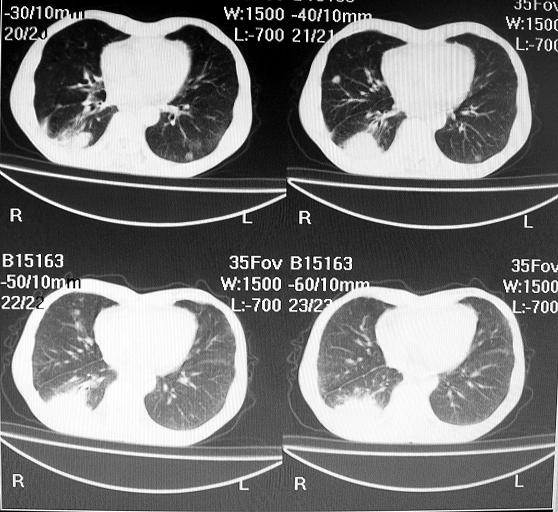

标题: CT10688:男63岁胸痛来诊 [打印本页]

标题: CT10688:男63岁胸痛来诊

男63岁胸痛来诊

右下肺周围性肺ca并双肺及右侧胸膜转移。[emb6]

右肺病灶前缘不平整,略呈分叶状,其后方胸膜下脂线消失且似有向胸壁浸犯,左下肺球形灶内可见不规则空洞影,余双肺内可见多枚结节影,结合病史支持考虑肺癌肺内转移胸膜转移,便双肺后部病灶倒也是结核好发区域,建议穿刺活检

左肺病灶内可见空泡征及典型的胸膜牵拉征,不排除原发周围型肺癌的可能.